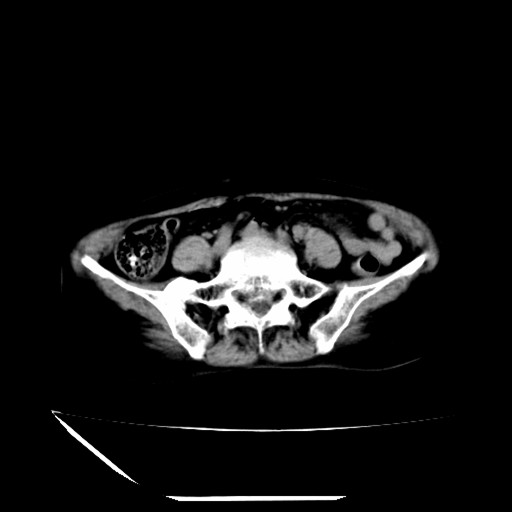

标题: CT16840:女-63岁,下腹部疼痛, [打印本页]

标题: CT16840:女-63岁,下腹部疼痛,

补充资料:血象是13.5,临床拟诊阑尾炎

本人诊断是右肾周围炎,阑尾炎,盆腔少许积液!

诊断右肾周围炎是因为我图像没有发完,诊断阑尾炎是因为相当于阑尾区连续两个层面可以看到增粗的阑尾显影。

支持阑尾炎!局部腹膜增厚,脂肪密度增高。应该手术治疗。